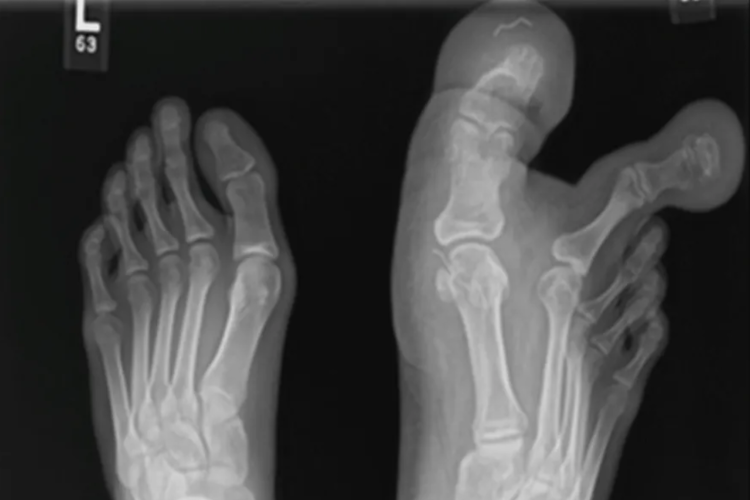

A adolescente, que não teve seu nome divulgado, tem um defeito congênito que causou a expansão dos ossos, tecidos do dedão e do segundo dedo pé direito. As imagens foram divulgadas por médicos.

“Radiografias simples e achados de ressonância magnética revelaram acúmulo de tecido adiposo ao redor do primeiro e segundo dedos, aspectos medial e lateral do primeiro metatarso, estendendo-se até o arco plantar medial do pé”, disse ele.